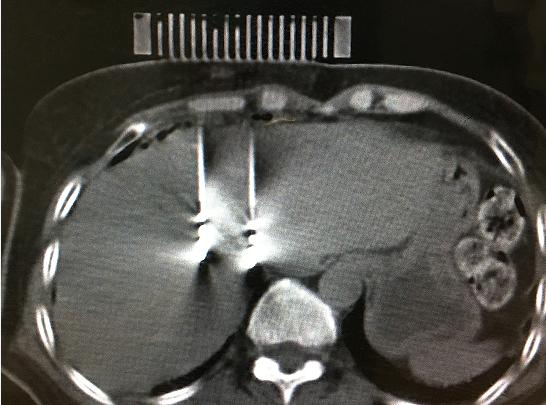

患者女性,57歲,肝癌術(shù)后5月復(fù)發(fā),病灶6.0cmx6.0cm大小,位于肝臟的右葉,靠近隔頂部,經(jīng)過多學(xué)科討論,決定實施經(jīng)皮微波消融術(shù),由于腫瘤體積較大,需要同時使用兩根消融天線進行多平面消融,為確保療效,兩根消融天線需要平行等距,但由于肝臟是不斷運動的臟器,徒手操作有一定技術(shù)難度,往往需要多次穿刺調(diào)整進針方向才能達到上述要求,為此,滕州市中心人民醫(yī)院腫瘤科張開賢主任醫(yī)師團隊借鑒既往采用模板引導(dǎo)放射性粒子植入的經(jīng)驗,創(chuàng)造性地將3D打印模板技術(shù)應(yīng)用于該例患者的消融治療,在模板引導(dǎo)下在兩個平面上平行等距插入兩根消融天線,經(jīng)過18分鐘的消融,腫瘤完全壞死,達到完全消融,患者正在術(shù)后康復(fù)之中。

3D打印模板引導(dǎo)消融的優(yōu)點:迅速將腫瘤與模板“固定”,防止因肝臟運動導(dǎo)致的穿刺不確定性;確保兩根消融天線平行等距,使熱場分布更加均勻;一次性穿刺布針成功,避免反復(fù)穿刺導(dǎo)致的腫瘤種植性轉(zhuǎn)移;模板對消融天線起到固定,防止因來回移動導(dǎo)致的消融天線位置的改變。據(jù)悉,這是國內(nèi)首例3D打印模板引導(dǎo)下的肝癌微波消融術(shù),這一技術(shù)的推廣應(yīng)用必將造福更多的腫瘤患者。(腫瘤一科 胡苗苗)